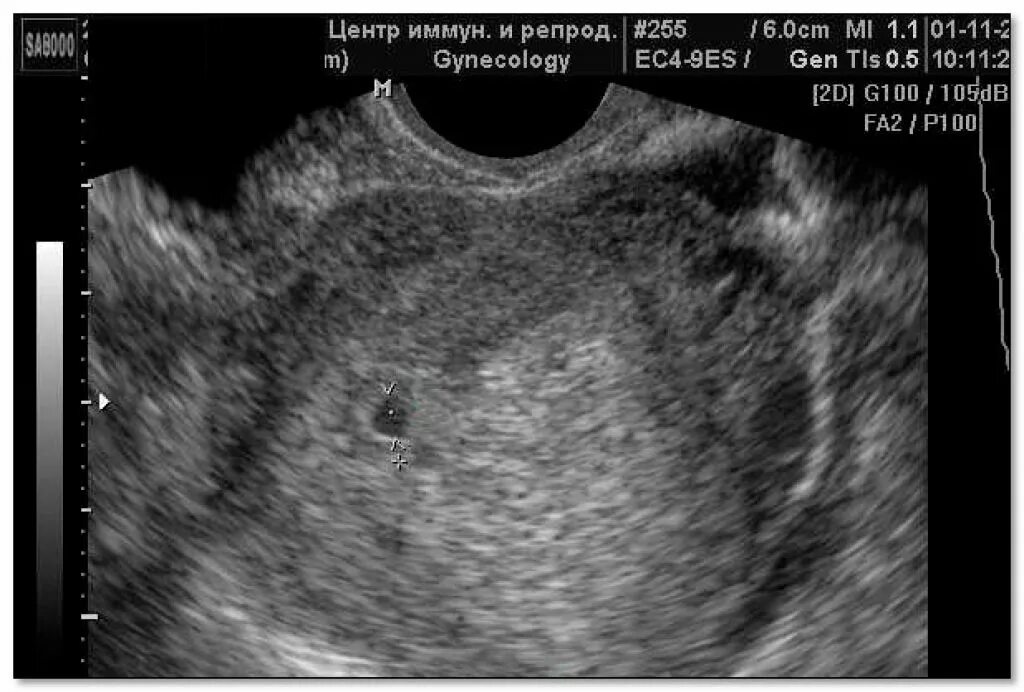

Узи беременности на ранних сроках 3-4 недели. узи беременности по неделям 4 недели. как на узи выглядит беременность 2-3 недели. узи на сроке 3-4 недели беременности.Узи 1 неделя беременности. узи 1-2 недели беременности. узи беременных 1 неделя. узи 1 недели беременности фото.Узи при беременности на ранних сроках. снимок узи беременности на ранних сроках. узи беременности на ранних сроках 1 неделя. снимок узи беременности на ранних сроках 5 недель.Узи 1.5 недели беременности. описание узи на ранних сроках беременности. узи 7,5 акушерская неделя беременности. 5 недель и 2 дня акушерской беременности узи.Узи для определения беременности на ранних сроках. эмбрион на ранних сроках узи. узи по беременности на ранних сроках.Ультразвуковое исследование беременности на ранних сроках. узи беременной на раннем сроке. ультразвуковое исследование при беременности раннего срока. узи при беременности на ранних сроках.Маточная беременность 4 недели узи. 4 недели беременности узи 4 недели беременности. беременность 2-3 недели фото плода узи. узи беременности по неделям 4 недели.Протокол узи беременности на ранних сроках. ультразвуковое исследование при беременности раннего срока. замершая беременность узи. узи малого таза беременность на ранних сроках.Узи беременности на ранних. беременночть ущи на ранн х сроках. снимки узи на ранних сроках.Узи беременности на 3 недели беременности. узи 3-5 недели беременности. ультразвуковое исследование беременности на ранних сроках. узи 2-3 недели беременности.Гравидарный эндометрий на узи. эндометрий с плодным яйцом. маточная беременность узи. беременность на 2-3 недели беременности на узи.Беременность на 2-3 недели беременности на узи. узи беременности на 3 недели беременности. узи 3 недели беременности от зачатия. снимок узи на 2 неделе беременности.Узи на сроке 4 недели беременности. снимок узи беременность малого срока 3 недели. маточная беременность 4 недели узи. маточная беременность 3 недели узи.Заключение узи о беременности 3-4 недели. узи беременности на ранних сроках заключение. узи малого таза на 4 неделе беременности. заключение узи 2 недели беременности.Узи двойни на ранних сроках беременности 5 недель. узи 3 недели беременности двойня. плодное яйцо на 2 недели беременности. узи беременность 2 плодных яйца.Покажет ли узи 1 неделю беременностиПлодное яйцо на 6 неделе беременности узи. плодное яйцо 2 недели срок по узи. узи плодное яйцо 6 недель двойня. узи на 5 акушерской неделе беременности.Заключение узи 4 недели беременности. на 3 недели беременности узи покажет беременность. узи 3-4 недели беременности. заключение узи о беременности 3-4 недели.Узи малого таза у беременных на ранних сроках. трансвагинальное узи 1 триместр. узи на ранних сроках беременности 1 триместр. узи беременности трансвагинально.Плодное яйцо на 6 неделе беременности. плодное яйцо на 2 недели беременности. плодное яйцо 4-5 недель беременности узи. узи 6 недель беременности плодное яйцо на узи.Узи двойни на ранних сроках 7 недель беременности. узи 7 недель беременности двойня. узи двойняшек на раннем сроке беременности. узи двойни на 7 неделе беременности фото.Узи на раннем сроке беременности 2 недели. ультразвуковое исследование при беременности раннего срока. узи беременности на ранних сроках 4-5 недель. узи 4 недели беременности.Узи на первой неделе задержки. узи на недельной задержке. первое узи после задержки. узи на беременность 1 день задержки.Узи двойняшек на 5 неделе беременности. узи на 4 неделе беременности двойня. узи двойни на ранних сроках беременности 5 недель. узи беременности двойней на 5 неделе беременности.Узи беременности на ранних сроках 1-2 недели. узи 2-3 недели беременности. узи 3 недели беременности от зачатия. беременность на 2-3 недели беременности на узи.Ультразвуковое исследование при беременности раннего срока. узи беременности на ранних сроках. узи по беременности на ранних сроках. заключение беременности 5 недель.Узи беременности на ранних сроках. узи при беременности на ранних сроках. ультразвуковое исследование беременности на ранних сроках. узи 4 недельной беременности.Протокол узи 5 недель беременности. неразвивающаяся беременность узи протокол. заключение узи при 4 недели беременности. узи 3 недели беременности заключение.Скрининг при беременности 5 недель узи плода. узи плода 4 недели беременности. узи беременность 6 недель норма ли 6.1 мм и 6.4 мм. узи 1.5 недели беременности.Плодное яйцо на узи на ранних сроках 2 недели. узи плодное яйцо в матке 4 недели. плодное яйцо на узи на ранних сроках беременности 2 недели. узи 5-6 недель плодное яйцо 12мм.Узи беременности на ранних сроках заключение. узи на выявление беременности на малых сроках. узи малого таза 6 недель беременности. ультразвуковое исследование при беременности раннего срока.Ультразвуковое исследование беременности на ранних сроках. узи матки беременность на ранних сроках. узи картина беременность малого срока. маточная беременность на узи на раннем сроке.Справка узи о беременности 4 недели. внематочная беременность узи заключение. заключение узи 4 недели беременности. заключение узи беременности 2-3 недели.Узи на 5 неделе беременности заключения. узи беременности 3-4 недели протокол. протокол узи на 3 неделе беременности. заключение узи по беременности 4-5 недель.Беременность малого срока. беременность малого срока на узи. узи на малых сроках беременности. уза маленький срок беременности.Узи 5-6 недель плодное яйцо 12мм. срок беременности по узи. плодное яйцо при беременности узи. узи 6 недель беременности.Беременность двойней узи на ранних сроках беременности. узи двухплодной беременности. узи близнецов на ранних сроках беременности. узи двойни на ранних сроках беременности 5 недель.Эмбрион 2-3 недели узи беременности. узи 1-2 недели беременности. узи 1 неделя беременности.Беременность на узи до задержки. узи по беременности на ранних сроках. узи беременной до задержки.Узи на первой неделе задержки. узи после двух недель задержки. узи на 5 день задержки. узи 1 неделя задержки.